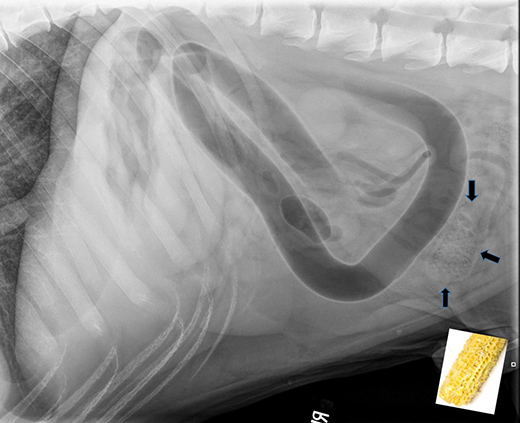

This radiograph shows a corncob in the gastrointestinal tract of a dog brought in recently to the Veterinary Health Center at Kansas State University. Photo courtesy of David Biller, professor and section head of radiology, K-State College of Veterinary Medicine. | Download this photo.

Swallowing the cob or pieces of the cob often causes a life-threatening obstruction of a dog's gastrointestinal tract, Nelson said, adding that the smaller the dog, the smaller the piece of cob that can cause this to happen. Corncobs also are not digestible, so if there is an obstruction of the gastrointestinal tract, abdominal surgery is usually needed to remove it.

"If smaller pieces of cob are in the stomach, they can sometimes be endoscopically removed," Nelson said. "But if dogs do not have the cob or pieces of cob causing the obstruction removed, it is usually fatal. Dogs that are brought to a veterinarian after they have been showing symptoms will also sometimes not survive, even with surgery."